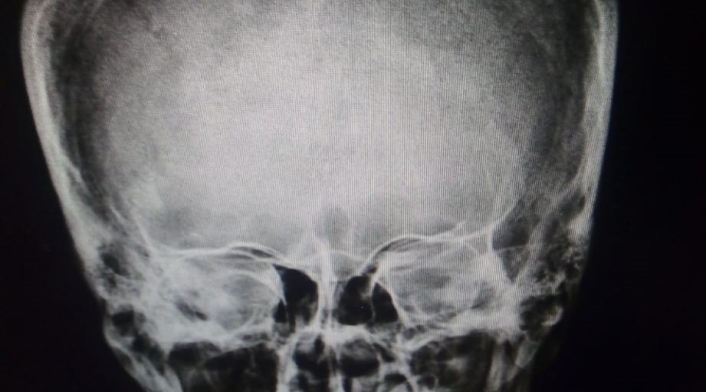

En una de las radiografías tomadas al paciente se observa la magnitud de la herida y la punta del cuchillo incrustada en su cráneo.

Según las autoridades, por tratarse de una lesión de gravedad y debido a la complejidad de la atención requerida, el paciente fue estabilizado en la USS Bosa y trasladado al hospital Occidente de Kennedy, donde le practicaron una tomografía que arrojó una herida de cinco centímetros de profundidad.

“El paciente sufrió una herida que le comprometía el seno longitudinal superior, por lo que debió realizarse una craneotomía para retirar el fragmento metálico y luego reparar el seno dural, por donde pasa el 20% por ciento de la sangre que va al cerebro en un minuto”, explicó Julio Cesar Sánchez, neurocirujano de la Subred Sur Occidente.